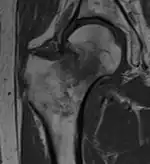

A case demonstrating a possible order of imaging in initially subtle findings:

X-ray showing a suspected compressive subcapital fracture as a radiodense line

CT scan shows the same, atypical for a fracture since the cortex is coherent

T1-weighted, turbo spin echo, MRI confirms a fracture, as the surrounding bone marrow has low signal from edema.